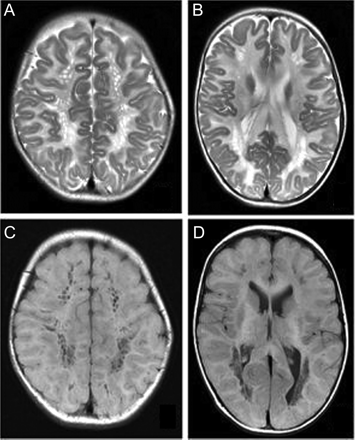

图1

脑部核磁共振成像

T2加权(A, B)和T1 (C, D)大脑的核磁共振显示严重和扩散T2 hyperintense和T1 hypointense白质信号变化表明Canavan疾病。U纤维存在的重要参与。白质内多个圆形或椭圆形囊性改变蜂窝的外表。这些囊性空间的径向排列表明Virchow-Robin空间的扩张由于海绵状白质变性。